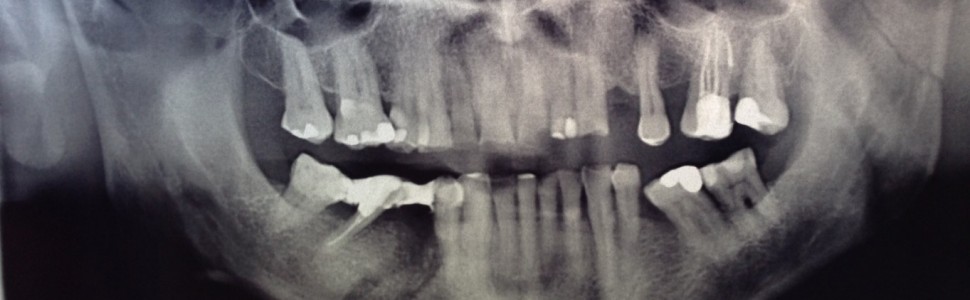

Artykuł przedstawia przypadek leczenia starszego pacjenta po udarze mózgu, który na skutek urazu stracił ząb 45 i doznał pęknięcia żuchwy po obu stronach. Zgłosił się do gabinetu po rozpoczęciu leczenia w Poradni Chirurgii Szczękowo-Twarzowej Szpitala Klinicznego w Łodzi, gdzie wykonano u niego szynowanie złamanej żuchwy. Niestety ten sposób leczenia nie odpowiadał pacjentowi.

The article presents a case of treatment of an elderly patient after a stroke, who lost tooth 45 as a result of the trauma and suffered a mandibular fracture on both sides. He came to me after starting treatment at the Clinic of Maxillofacial Surgery of the Hospital in Łódź, where he underwent splinting of a broken mandible. Unfortunately, this method of treatment did not suit the patient.